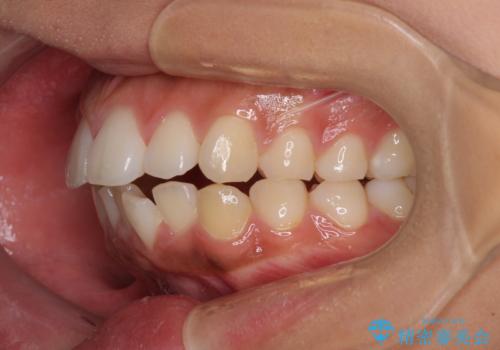

- 出っ歯と口の閉じにくさ、デコボコを気にして来院された患者様です。

口元の突出感を改善するため、上下左右第一小臼歯4本の抜歯を行い、ワイヤー装置による矯正治療を行うこととしました。

舌の突出癖により上下前歯は非接触であり、非常に前方に飛び出している状態でした。

舌のトレーニングをしっかりと行っていただき、口の閉じやすい歯並びに仕上げることができました。